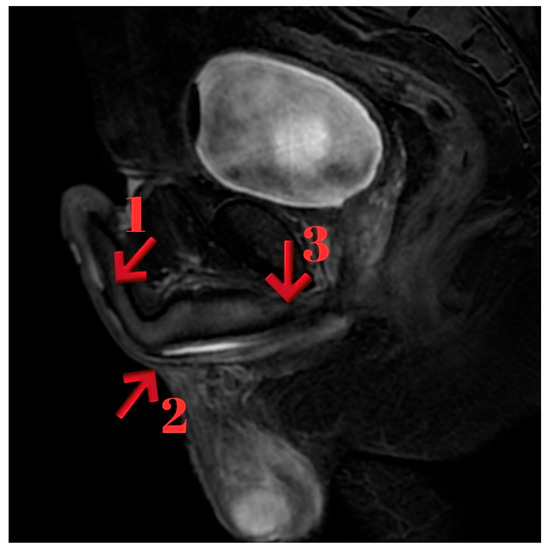

Background/Objectives: Conventional imaging modalities are often inadequate for evaluating the proximal extent of anterior obliterative urethral strictures. Magnetic Resonance Imaging (MRI), with its superior soft tissue resolution, provides detailed anatomical insights and significantly contributes to surgical planning in such cases. Methods: Four male patients aged 26–63 years with anterior obliterative urethral strictures were evaluated using MRI in addition to conventional imaging. All MRI scans were performed following a modified Joshi protocol. Clinical data, MRI findings, and surgical outcomes were retrospectively reviewed. Results: MRI successfully delineated stricture length, location, periurethral fibrosis, and proximal urethral status in all cases, correlating well with intraoperative findings. Case 1 showed a 2 cm proximal bulbar obliteration, excised with end-to-end anastomosis. Case 2 had a 2.5 cm distal bulbar stricture, managed similarly. Case 3 revealed multi-segmental strictures, treated with a combination of anastomosis, graft, and Kulkarni urethroplasty. Case 4 demonstrated a rare 9 cm distal penile obliteration with preserved proximal urethra, treated with anastomotic repair. MRI provided critical anatomical detail for surgical decision-making. Conclusions: MRI is a valuable imaging modality for the evaluation of anterior obliterative urethral strictures, particularly when the proximal extent of the stricture cannot be visualized with conventional imaging techniques. In our case series, MRI enabled precise delineation of the stricture length and surrounding anatomical structures, which was critical for selecting the most appropriate surgical approach. Full article

Figure 1